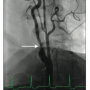

arch aortogram revealed a Type I aortic arch with no significant atheroma (Figure 1). A Simmons 2 catheter (AngioDynamics) was used to selectively engage the right common carotid artery by looping the catheter in the right coronary cusp. A stiff-angled Glidewire (Terumo) was then used as an anchor in the right external carotid artery (Figure 2A) and a Pinnacle Destination sheath (Terumo) advanced into the right common carotid artery (Figure 2B). Selective angiogram confirmed an 80% stenosis of the right internal carotid artery (Figure 3). An Emboshield distal embolic protection device (Abbott Vascular) was deployed in a straight segment in the distal right internal carotid artery. After pre-dilation with a Viatrac 4.0 x 20 mm

balloon (Abbott Vascular), an Xact 6-8 x 30 mm self-expanding stent (Abbott Vascular) was deployed in the right internal carotid artery, and post-dilated using a Viatrac 5.0 x 20 mm balloon. Final angiogram confirmed excellent angiographic result and brisk flow (Figure 4). The patient was discharged home the following day after initiation of dual antiplatelet therapy indefinitely.